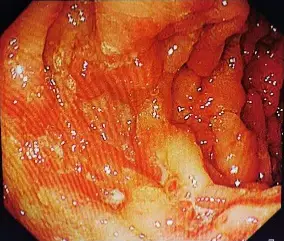

哎呀,说到克罗恩病,这可不是个让人轻松的话题啊!这病啊,就像个顽皮的小鬼,总是悄无声息地侵入我们的生活,让人的肚子疼得死去活来。西医的治疗方法虽然科学,但有时候总觉得少了点什么,让人心里空落落的。

而且啊,听说中西医结合不仅能缓解症状,还能调整身体的整体状态,这不就是传说中的“治标又治本”吗?每次去医院,看到那些医生认真地给我把脉、开方子,心里就觉得特别踏实。虽然治疗过程有时候会有点小痛苦,但想到未来可能不再被疼痛困扰,就觉得一切都值了。

这种疗法,就像是给克罗恩病患者打开了一扇新的大门,让我们看到了不一样的希望。